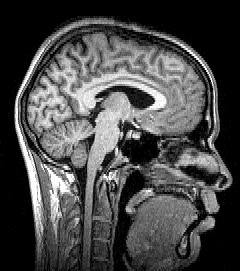

Tomography is imaging by sections or sectioning that uses any kind of penetrating wave. The method is used in radiology, archaeology, biology, atmospheric science, geophysics, oceanography, plasma physics, materials science, cosmochemistry, astrophysics, quantum information, and other areas of science. The word tomography is derived from Ancient Greek τόμος tomos, "slice, section" and γράφω graphō, "to write" or, in this context as well, "to describe." A device used in tomography is called a tomograph, while the image produced is a tomogram.

Although MRI (magnetic resonance imaging), optical coherence tomography and ultrasound are transmission methods, they typically do not require movement of the transmitter to acquire data from different directions. In MRI, both projections and higher spatial harmonics are sampled by applying spatially-varying magnetic fields; no moving parts are necessary to generate an image. On the other hand, since ultrasound and optical coherence tomography uses time-of-flight to spatially encode the received signal, it is not strictly a tomographic method and does not require multiple image acquisitions.